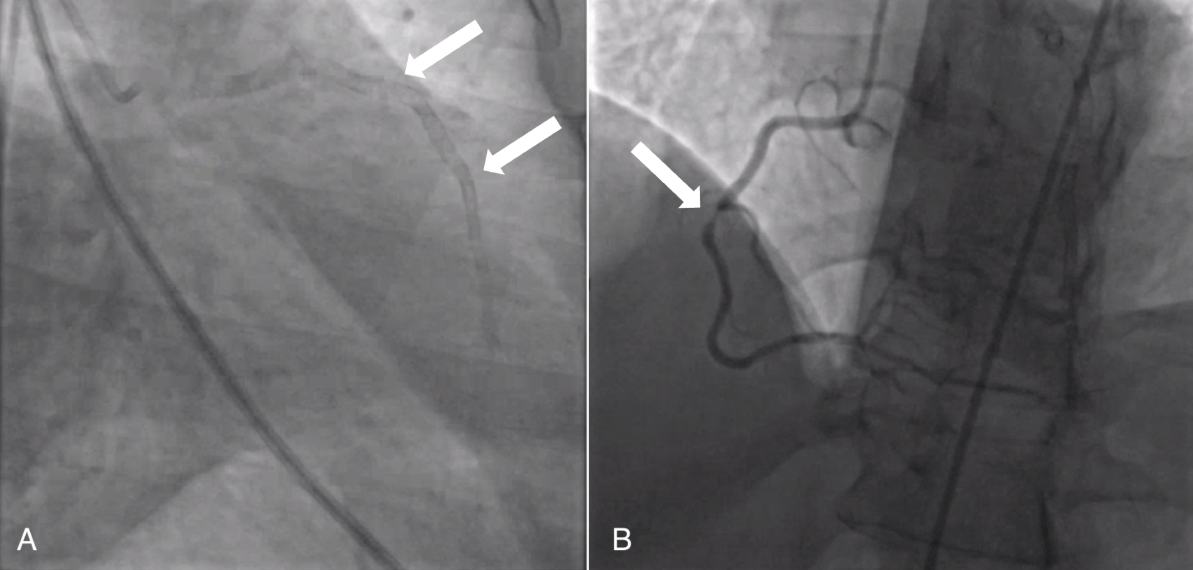

The patient was a 54-year-old woman with type 2 diabetes mellitus, metabolic syndrome, and significant coronary artery disease, who had undergone multiple percutaneous coronary interventions (PCI) and presented with non-ST-segment elevation myocardial infarction. A coronary angiography revealed in-stent restenosis (ISR) in eight drug eluting stents throughout the entire left anterior descending artery (LAD) (figure 1A). In addition, the right coronary artery (RCA) was 90-99 percent stenosed and the left circumflex (LCX) artery was diseased (figure 1B). An echocardiography showed a left ventricular ejection fraction of 45 percent.

Figure 1A: Coronary angiography depicting (A) stents throughout the entirety of the LAD (white arrows)

Figure 1B: 90-99 percent RCA occlusion (white arrow)